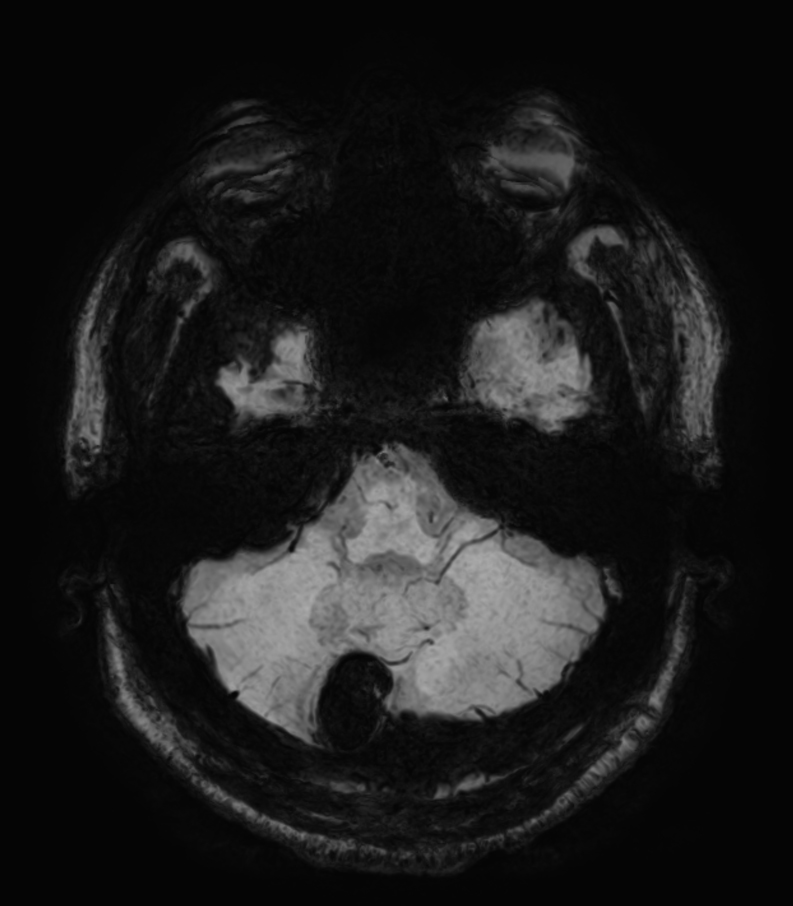

SWIp (minIP)